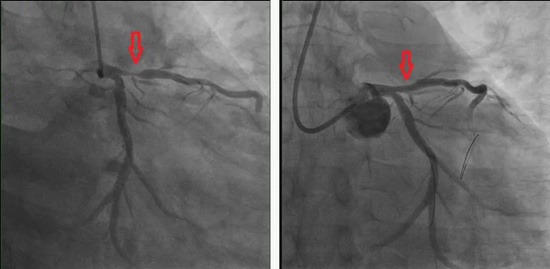

患者陈先生今年54岁,2天前休息时出现前胸疼痛并伴有胸闷不适。到我院就诊时,行冠脉CTA检查显示为冠心病、左主干末端-前降支近端不稳定斑块形成并重度狭窄。于是马上入院治疗,并在住院当晚再次发作严重心绞痛。考虑到患者病情高危,祁家祥主任第二日上午马上为患者进行了急诊冠脉造影检查,检查结果显示:前降支开口-近端可见不稳定斑块,最重处狭窄90%。患者随时可能血管闭塞导致猝死。

(术前术后对比)